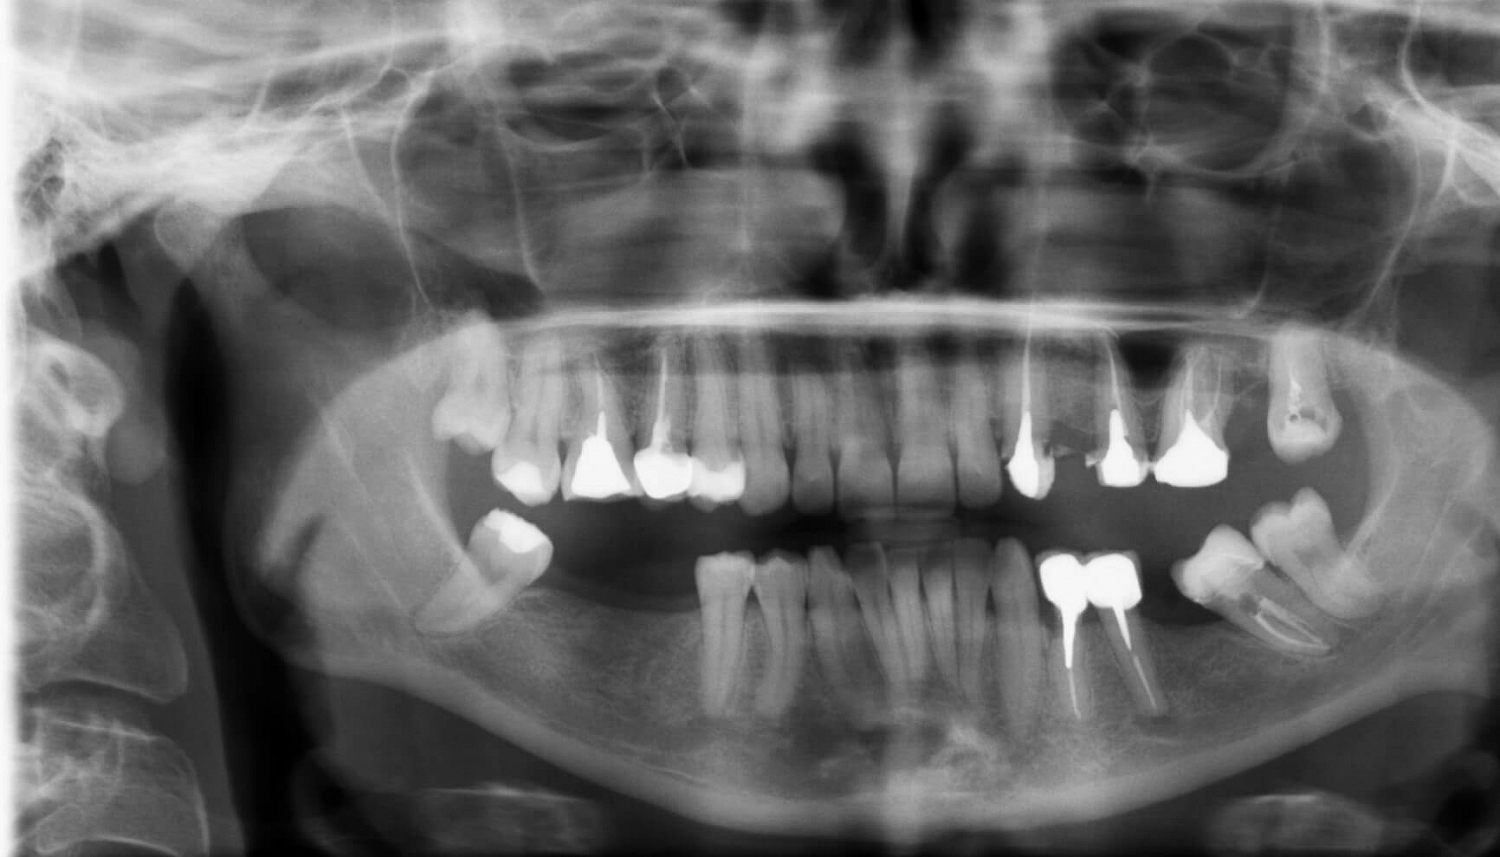

Пациент направлен из другой клиники для проведения костной пластики на нижней челюсти справа.

Костная пластика необходима для увеличения ширины альвеолярного отростка (имплантация в этой зоне затруднена из-за дефицита костной ткани по ширине). Данная операция позволит поставить имплантаты большего диаметра и даст более долгосрочный прогноз на стабильность устанавливаемых имплантов и будущих ортопедических конструкций.

• Фото №1. ОПТГ перед операцией: Операция по забору костного блока проведена под комбинированным обезболиванием (сочетание местного анестетика и седации). Костный блок взят в ретромолярной области с правой стороны.

• ОПТГ после операции: на нем видны три костных блока зафиксированных на альвеолярном отростке при помощи винтов.

Данная операция позволит увеличить объем кости в данный области и через 3-4 месяца позволит провести операцию по установке дентальных имплантов.